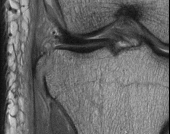

Question 11

A 9-year-old boy sustains a distal femur fracture. Radiographs demonstrate a fracture line propagating along the physis and exiting through the metaphysis, producing a small metaphyseal bone fragment (Thurston-Holland fragment). Based on the Salter-Harris classification, what type of fracture is this, and what is the typical expectation regarding growth arrest?

Explanation

A fracture that propagates through the physis and exits through the metaphysis (creating a Thurston-Holland fragment) is a Salter-Harris Type II fracture. It is the most common physeal fracture pattern. Because the germinal layers of the physis remain attached to the epiphysis, the general prognosis for growth is good. However, one must recognize that Type II fractures of the distal femur inherently carry a high risk of growth arrest (up to 40-50%) compared to other locations.